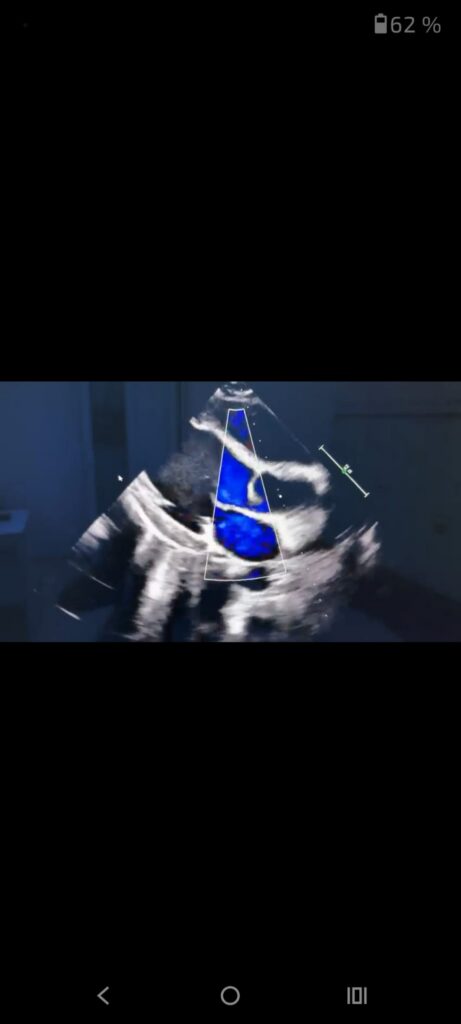

- Ecocardiografia pediatrică (Eco cord) – investigație imagistică vitală. Promoție în luna decembrie: preț redus de la 500 lei la 400 lei.

Prin aceste investigații, menționează specialiștii, medicul poate vedea în timp real modul în care funcționează inima, ritmul cardiac, răspunsul la efort. Medicul poate depista eventualele afectări structurale, oferind baza pentru un plan de tratament personalizat.